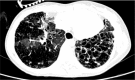

Primary ciliary dyskinesia (PCD) is a genetic disorder of ciliary structure or function. It results in mucus accumulation and bacterial colonization of the respiratory tract which leads to chronic upper and lower airway infections, organ laterality defects, and fertility problems. We review the respiratory signs and symptoms of PCD, as well as the screening tests for and diagnostic investigation of the disease, together with details related to ciliary function, ciliary ultrastructure, and genetic studies. In addition, we describe the difficulties in diagnosing PCD by means of transmission electron microscopy, as well as describing patient follow-up procedures.